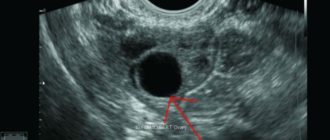

Показывает ли беременность на ранних сроках до задержки на УЗИ: диагностика, расшифровка, определение на